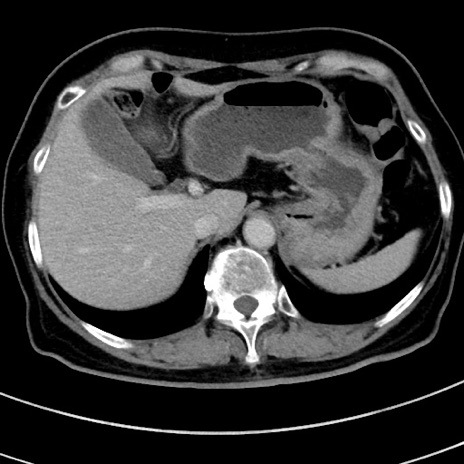

症例9(横断像)

【症例】 60歳代女性

【主訴】むかつき、みぞおちの痛み

【現病歴】3日前よりむかつきがあり、食事がとれない。

【既往歴】糖尿病

【身体所見】発熱なし、心窩部圧痛軽度あるも、腹膜刺激症状なし。

【データ】WBC 7400、CRP 1.92